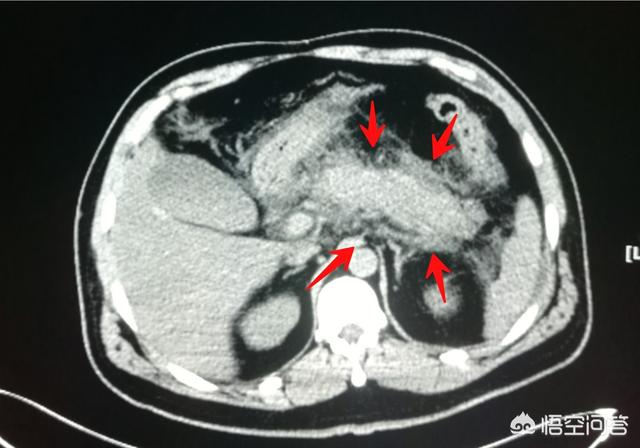

像这位38岁男性患者,参加同学聚会,玩命地喝,第二天就剧烈上腹痛,向后背放射,同时有腹胀和恶心呕吐,急诊CT显示很典型的胰腺炎,体积增大,轮廓毛糙,周围脂肪间隙密度增高,化验检查血清淀粉酶明显升高。

符合以下3项特征中的2项即可诊断胰腺炎:(1)与胰腺炎相符合的腹痛;(2)血清淀粉酶和(或)脂肪酶活性至少高于正常上限值3倍;(3)腹部影像学检查符合胰腺炎影像学改变。

上面这位患者比较不错,第9天复查的时候已经显示吸收好转了。他还很不好意思的表示,以后喝酒要节制了,这次赔大发了。